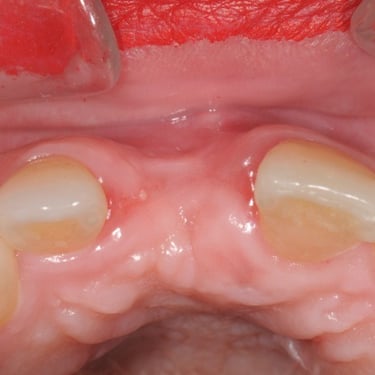

Edentulismo completo

El edentulismo completo es la ausencia total de dientes en una o ambas arcadas.

Los pacientes tienen dificultad para masticar, hablar y pueden sentirse incómodos con su apariencia.

El tratamiento puede incluir la colocación de una prótesis completa sobre implantes, proporcionando una solución fija y estable